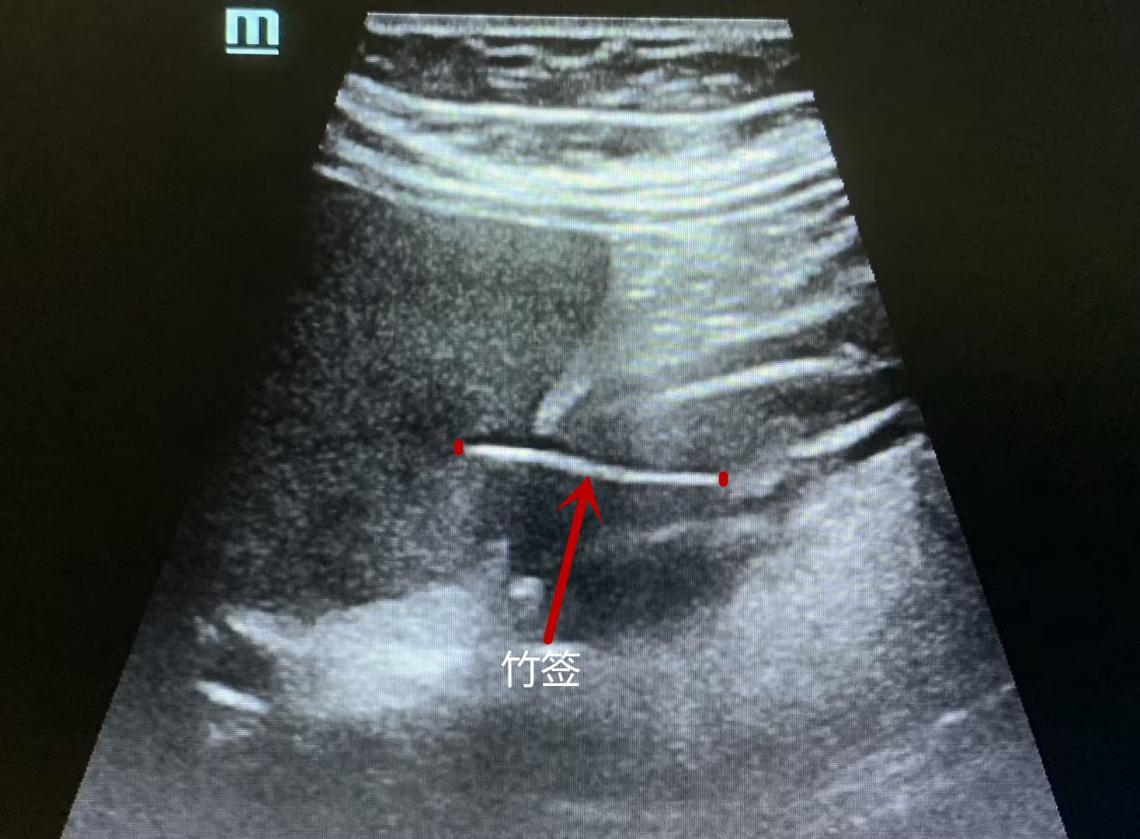

超声科谭庆亭医师反复检测,在患者的胃窦处发现了一个细细长长的异物,经张华斌主任当场会诊后,明确了诊断。此时,患者才努力地回想起,自己发病的前一天曾用竹签吃过包子。超声检查发现这根竹签已经刺破了胃壁,扎入了肝脏。“胃镜没发现是因为这根竹签的位置很特殊,它穿出了黏膜层,位于黏膜下。”超声科主任张华斌解释说。

张华斌主任讲解异物的位置

而CT和PET/ CT作为临床判别肿瘤的重要手段,主要依靠对组织密度和代谢情况的识别来得出结果,对金属类异物很敏感,但对于竹制品这类与人体软组织密度相似的异物却很难辨别出来。“这根小竹签无论是质地还是位置,对于医学检查来说都十分‘狡猾’。局部增厚的胃壁、肝脏的局灶低回声,以及周围的淋巴结,这些都是异物引起的炎性反应,容易判别为肿瘤倾向。”张华斌解释说。